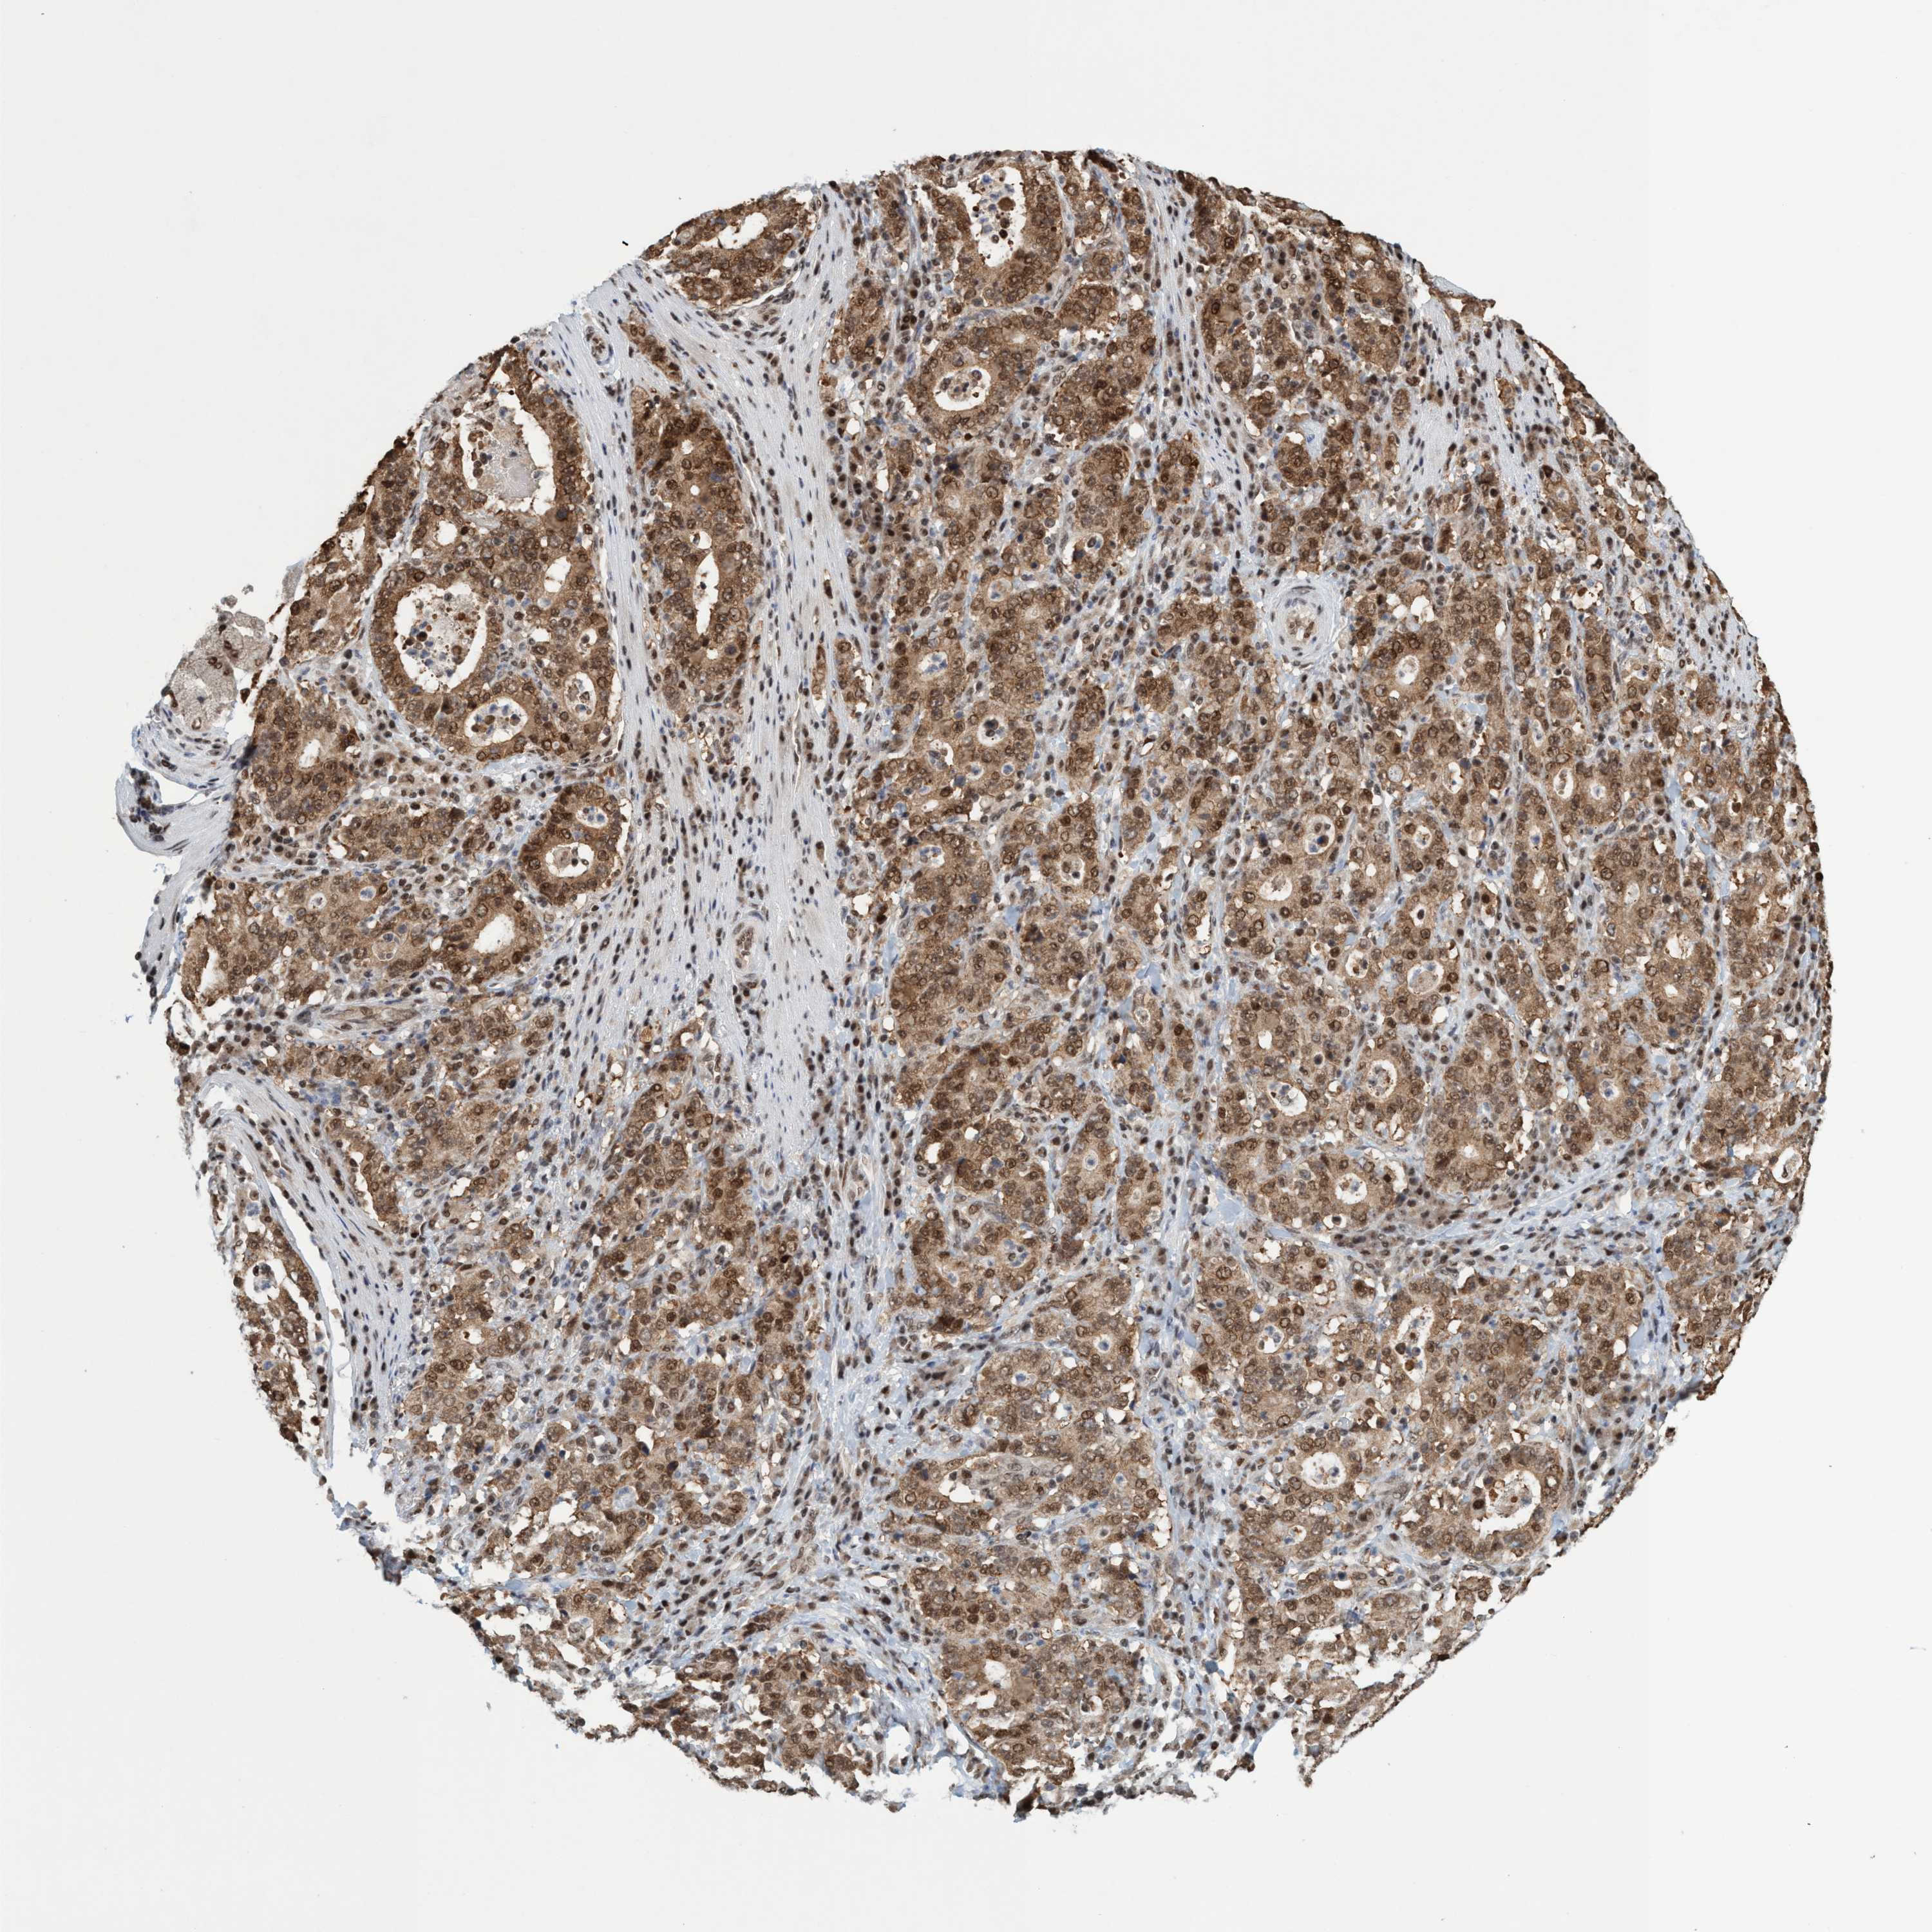

STOMACH CANCER - Protein expressioni

A mouse-over function shows sample information and annotation data. Click on an image to view it in a full screen mode. Samples can be filtered based on level of antibody staining by selecting one or several of the following categories: high, medium, low and not detected. The assay and annotation is described here.

Antibody stainingi

Antibody staining in the annotated cell types in the current human tissue is reported as not detected, low, medium, or high, based on conventional immunohistochemistry profiling in selected tissues. This score is based on the combination of the staining intensity and fraction of stained cells.

Each image is clickable and will lead to virtual microscopy that enables deeper exploration of all samples and also displays staining intensity scores, fraction scores and subcellular localization as well as patient and tissue information for each sample.

Antibody HPA021557

Antibody HPA024646

Staining

High

Medium

Low

Not detected

Intensity

Strong

Moderate

Weak

Negative

Quantity

>75%

75%-25%

<25%

None

Location

Nuclear

Cytoplasmic/membranous

Cytoplasmic/membranous,nuclear

Adenocarcinoma, NOS